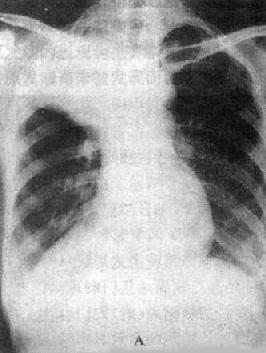

(1)一侧性肺不张:X线现为患侧肺野均匀致密,纵隔向患侧移位,肋间隙变窄(图3-1-7)。健侧肺可有代偿性肺气肿。

图3-1-7 一侧性肺不张

左侧支气管阻塞引起左侧全肺不张,显示左侧肺野均匀致密,

纵隔向患侧移位,肋间隙变窄,膈升高